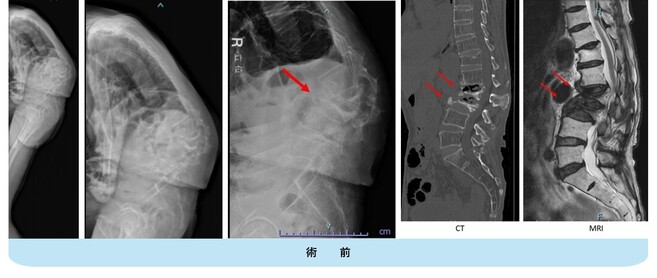

思春期特発性側弯症が高度に進行した症例です。最大側弯角度は113°であり、100°を超える側弯の手術は一般的に神経合併症が危惧されます。神経合併症を極力防ぐため、また侵襲を低減する目的で、同じ入院期間に2回に分けて段階的に矯正手術を行いました。1回目に最も側弯の強い箇所に対して側方から椎体間解離を行い、2回目に後方から全体のバランスが良くなるように慎重に矯正固定術を施行しています。

神経合併症はなく、術後の最大側弯角度は15°に改善(矯正率:87%)、背中の大きなコブも無くなっているのが分かります(赤矢印)。神経合併症が発生しないように慎重に手術を行うのは当然ですが、側弯を治すだけでなく横から見た姿勢を治すことにも留意しています。